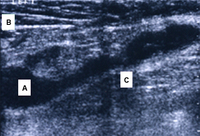

Popliteal cyst lying in its most common location in the posteromedial popliteal fossa (A), dissecting through the deep fascia (B) and the medial head of the gastrocnemius muscle (C)

Adapted from Labropoulos N, Shifrin DA, Paxinos O. New insights into the development of popliteal cysts. Br J Surg. 2004;91:1313-1318; used with permission